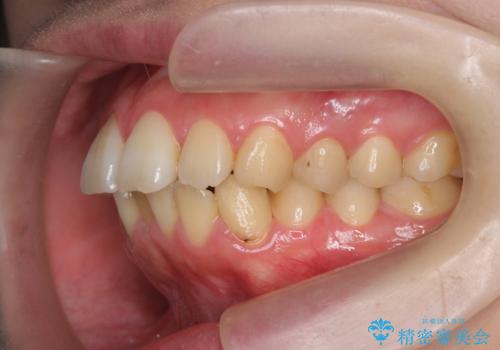

歯を抜かずに行う前歯の角度の改善

- 歯を抜かずに前歯の角度を改善したい、と矯正治療を希望され来院されました。

可及的に前歯部にIPR(歯間の削合)を行い、抜歯をせずマウスピース矯正システムインビザラインで歯の排列を行っていく治療計画としました。

治療の前後を比べると、がたつきや歯の角度が改善したことがしっかりと確認されました。